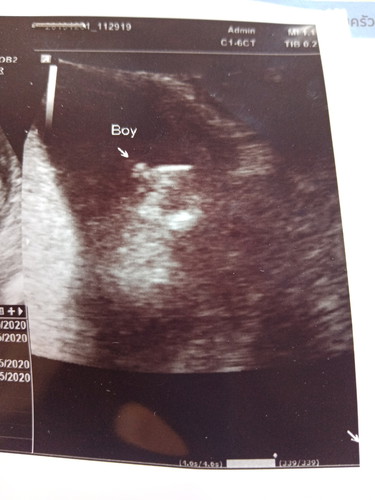

เดือนที่แล้วหมอบอกผุ้ชายค่ะเดือนนี้หมอบอกผุ้หญิงค่ะเพื่อนๆๆคิดว่ายังไงค่ะ

ถ้าชายน่าจะชัวร์กว่านะคะ หมอน่าจะเห็นจู๋น้องแล้ว

คุณแม่ก็อย่กได้ชายค่ะ